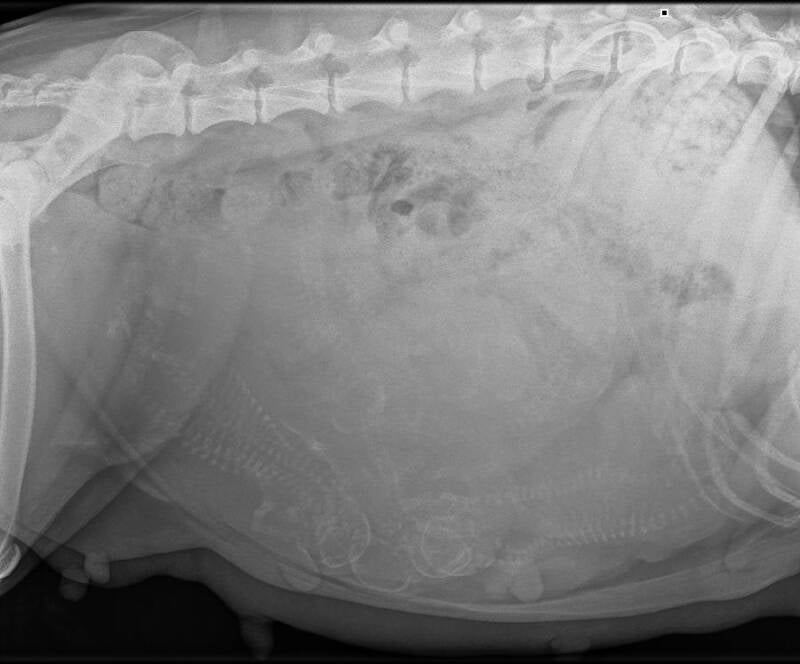

We went to the vet today to have an x-ray taken. Something came up on Friday, which meant we had to move the appointment to Wednesday.

Xanthy enjoyed being at the vet, because she got a lot of attention. I helped take the x-ray. Of course, I had to wear protective clothing for this. Then I stood by her head to make sure she stayed calm.

She did great. She was panting a lot, though.

It's quite hard to see in this picture, but at the vet we could see it well. The vet counted 9 puppies. I didn't expect that. I kind of assumed 6 puppies, but I was happy to expect it.

She also has a huge belly. And it's no wonder she doesn't like walking. She has gained quite a bit of weight, but she is definitely not too fat. She could really use more kibble.